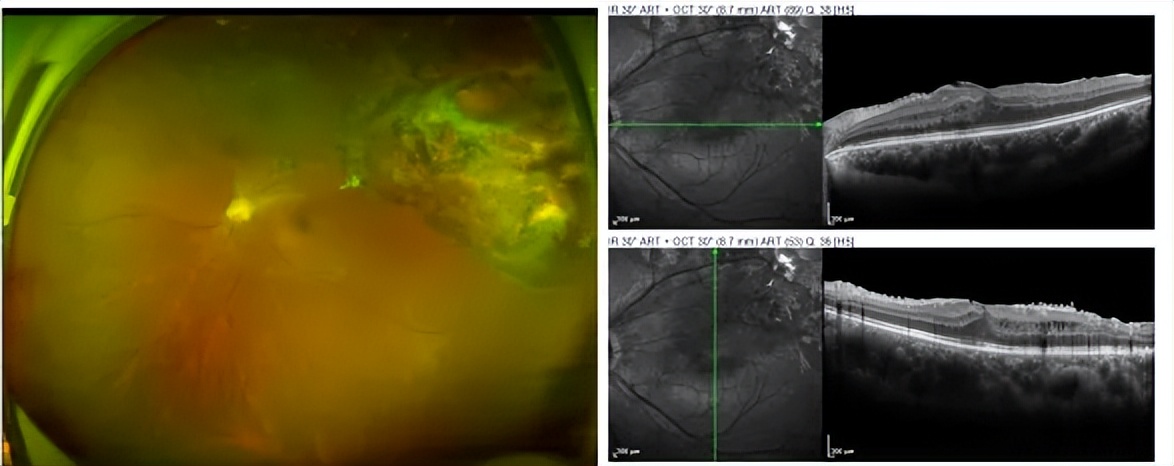

图2. 硅油取出,剥除黄斑前膜及牵拉增殖膜后3个月,裸眼视力0.5。